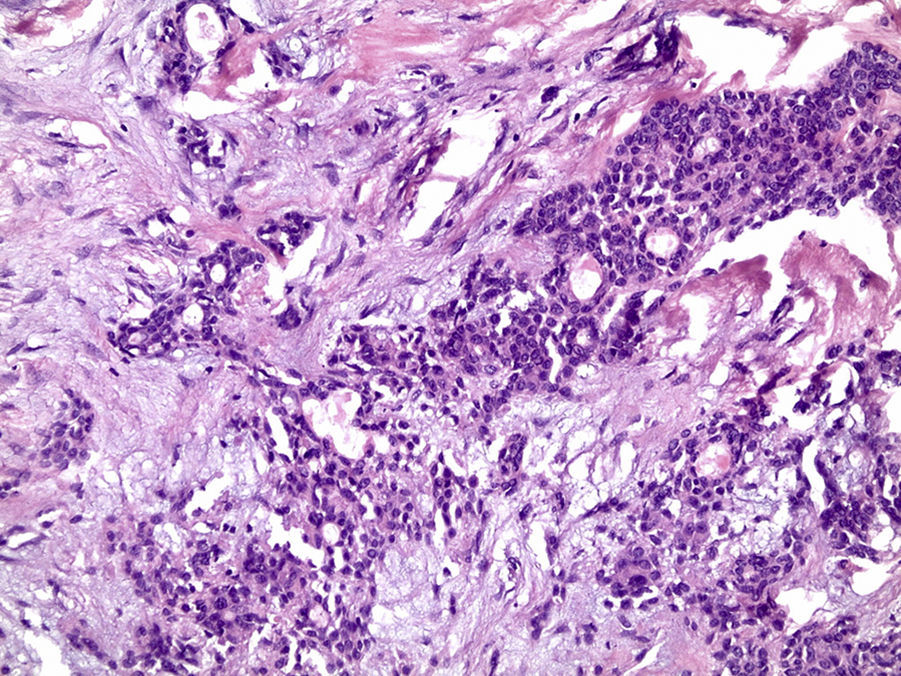

Os cortes histológicos, corados em hematoxilina e eosina, mostraram neoplasia de glândula salivar benigna, constituída por células epiteliais e mioepiteliais, parcialmente envolvida por fina cápsula de tecido conjuntivo fibroso (fig. 5). As células epiteliais encontravam‐se formando lençóis ou estruturas ductiformes, enquanto as células mioepiteliais formavam áreas mixoides, hialinas (fig. 6) ou exibiam aspecto plasmocitoide (fig. 7). O diagnóstico de adenoma pleomórfico foi confirmado. Paciente queixou‐se de desconforto no palato quando se alimentava, durante as 2 primeiras semanas após cirurgia. O paciente está sendo acompanhado clinicamente e, 2 anos após a cirurgia, não apresenta sinais de recidiva da lesão (fig. 8).

Os cortes histológicos mostraram neoplasia benigna de glândula salivar, envolvida por cápsula de tecido conjuntivo fibroso (fig. 14). O parênquima neoplásico é constituído por células epiteliais dispostas em lençóis e estruturas ductiformes, além de células mioepiteliais formando áreas mixoides e hialinas (fig. 15) ou apresentando‐se com morfologia plasmocitoide (fig. 16). O diagnóstico de adenoma pleomórfico foi confirmado. A paciente relatou ausência de dor no pós‐operatório e manteve utilização da placa de acrílico por 4 semanas. A paciente encontra‐se em acompanhamento e o exame clínico após 2 anos da remoção cirúrgica mostrou adequada cicatrização e ausência de sinais de recidiva da lesão (fig. 17).